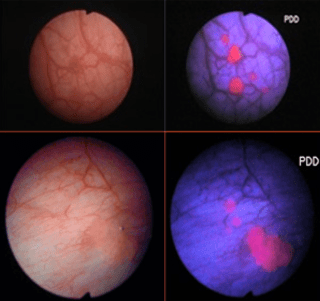

DIAGNOSTICO FOTODINAMICO PDD

Utiliza la luz azul en combinación con un fotosensibilizador – Acido 5 Aminolaevulinico (5-ALA) o Acdio Hexaminolaevulinico (HAL) – bsado en estudios que demostraron que existían tumores que no podían detectarse mediante luz blanca convencional.

El PDD tiene una mayor sensibilidad (92 % vs 71 %) para la detección del CIS que la luz blanca; aunque la especificidad es francamente inferior (63 %Ç vs 81 % )

MU POINT sobre el PDD

Un Estudio Prospectivo Randomizado NO CONFIRMO mayores tasas de detección en pacientes con Citología de orina positiva conocida previamente.

Los estudios Prospectivos Randomizados son controversiales al intentar demostrar una disminución en las tasas de recurrencia con el uso de RTU V utilizando ALA.

Tiene Falsos Positivos en relación a la inflamación post RTU V y por BCG incluso tras 3 meses de la terapia.

Un Metaanalisis demostró disminución del 10 % en las tasas de recurrencia ea los 12 meses en todos los grupos.

Permanece por aclarar si disminuye las tasas de progresión y de supervivencia.